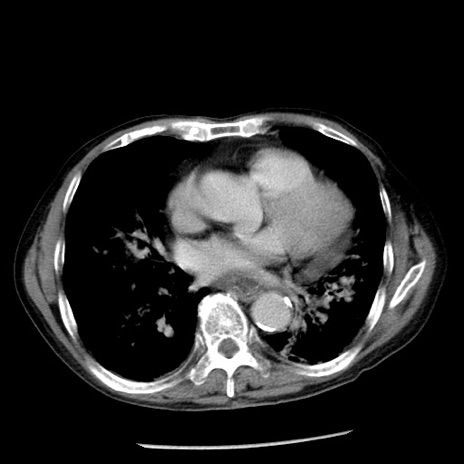

症例26(横断像)

【症例】80歳代男性

【主訴】嘔吐

【現病歴】昨晩2回嘔吐あり、今朝になっても嘔吐あり。来院。

【既往歴】胃潰瘍

【身体所見】意識清明、BT 37.6℃、BP 166/95mmHg、HR 100bpm、SpO2 97%、腹部:平坦・軟、腸蠕動音聴取良好、圧痛なし。

【データ】WBC 21900、CRP 1.46